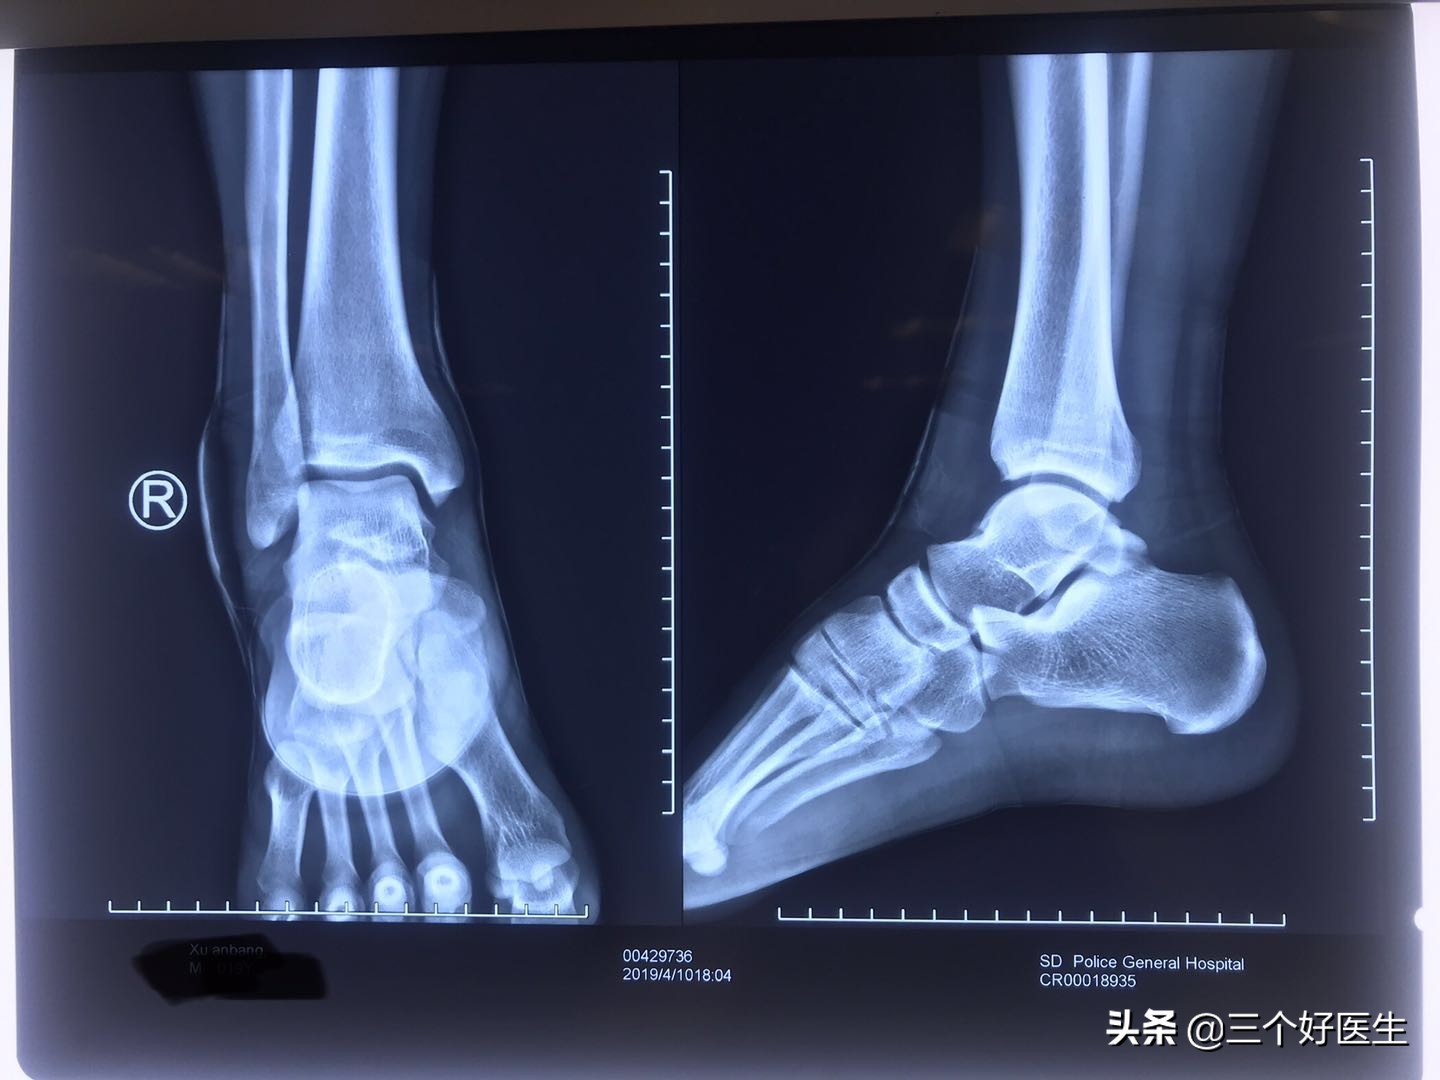

步骤二:去医院拍X光片,此处注意首选X光,因为主要看骨头是否有异常和损伤,CT和MR在此处并不占优势,而且后二者在医院排队和出片的时间都比较晚,X光一般半个小时就出来了,在去医院的时候要选择挂急诊科,这样可以更加的快速。在这里提醒大家不要为了省钱而不去拍片,这个过程省略不了,请务必重视。

X光片未见异常

报告未见异常